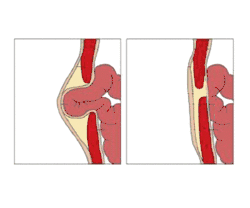

An umbilical hernia is a health condition where the abdominal wall behind the navel is damaged. It may cause the navel to bulge outwards—the bulge consisting of abdominal fat from the greater omentum or occasionally parts of the small intestine. The bulge can often be pressed back through the hole in the abdominal wall, and may "pop out" when coughing or otherwise acting to increase intra-abdominal pressure. Treatment is surgical, and surgery may be performed for cosmetic as well as health-related reasons.

Normally, the abdominal muscles converge and fuse at the umbilicus during the formation stage, however, in some cases, there remains a gap where the muscles do not close and through this gap the inner intestines come up and bulge under the skin, giving rise to an umbilical hernia. The bulge and its contents can easily be pushed back and reduced into the abdominal cavity.